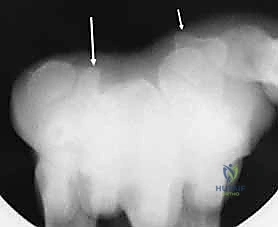

- الأشعة السينية بوضعيات خاصة: أخذ صور بأكثر من زاوية لفك تراكب العظام.

- الأشعة المقطعية (CT Scan): المعيار الذهبي لتشخيص كسور عظام الرسغ المخفية وتحديد حجم التفتت والتزحزح.

تحت توجيه الأشعة السينية المباشرة داخل غرفة العمليات (C-arm)، يتم إرجاع قطع العظم المكسورة إلى مكانها الطبيعي بدقة متناهية لا تقبل الخطأ حتى بمليمتر واحد، لأن أي اعوجاج سيؤدي إلى خشونة مبكرة في المفصل.

* أسلاك كيرشنر (K-wires): تُستخدم للتثبيت المؤقت أو في الكسور البسيطة.

* المسامير بدون رأس (Headless Compression Screws): تُدفن بالكامل داخل العظم لتجنب احتكاكها بالأوتار، وتوفر ضغطاً ممتازاً لسرعة التئام الكسر.